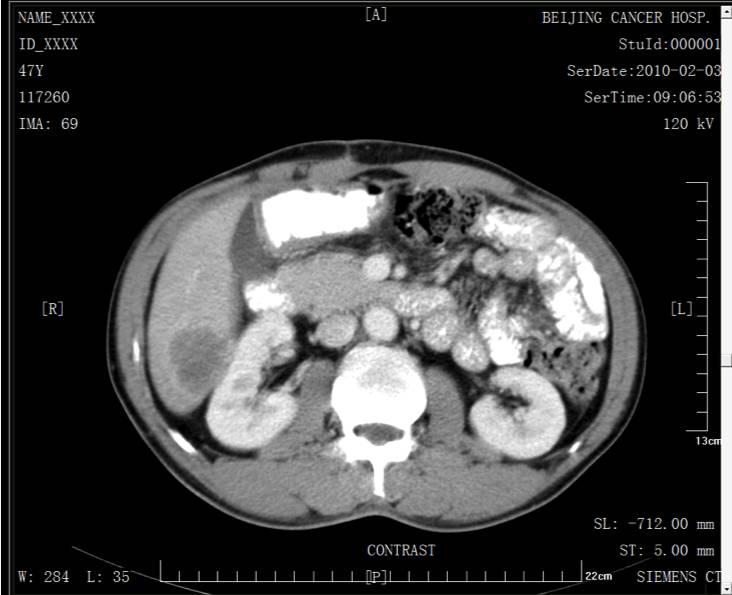

2010.02.04腹部CT示肝S6占位,大小4.0x3.8cm,符合肝转移瘤改变。

胸部、盆腔CT未见异常。CEA 16.35ng/ml。肝转移评估可切除。